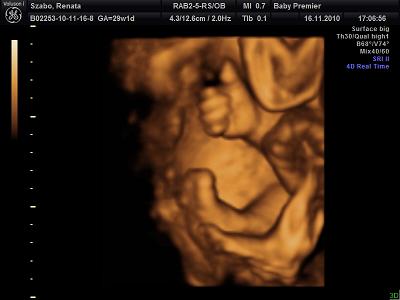

Itt mutatja hogy minden rendben mami!A lábacskája is látszik.

A lényeg hogy az arca elött nem csak a keze van hanem a lába is.